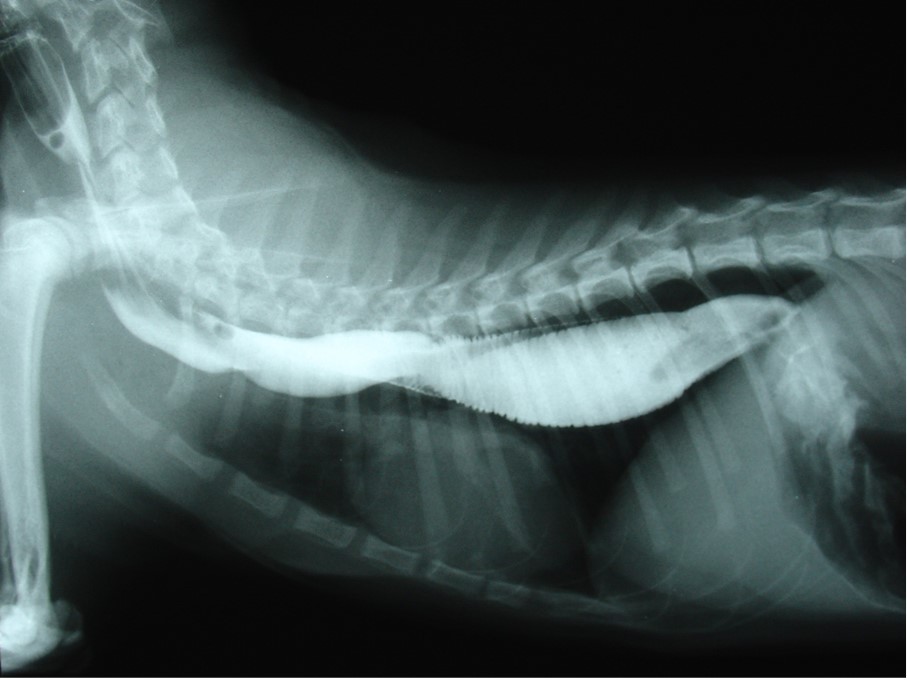

What is this?

•This is a cat with barium – dilation of the oesophagus through the whole length.